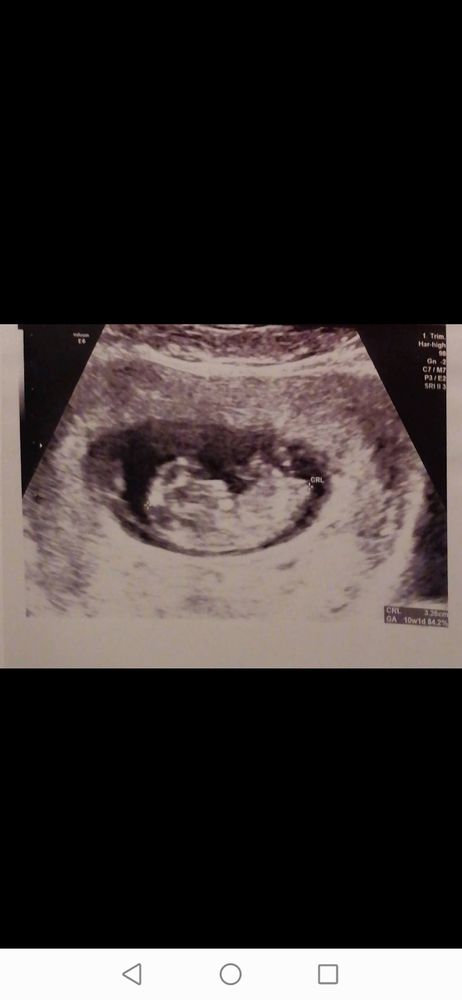

Akmaral Davletyarova

Настасья, да 9 недель тут и 5 дней спасибо что ответили, очень интересно узнать но придется ждать

Akmaral Davletyarova, узи по животу? Если по животу я бы предположила мальчика. Но это все не гарантия. Тут девочки обсуждали эту тему Рамзи из 100 только у 20 сошлось.